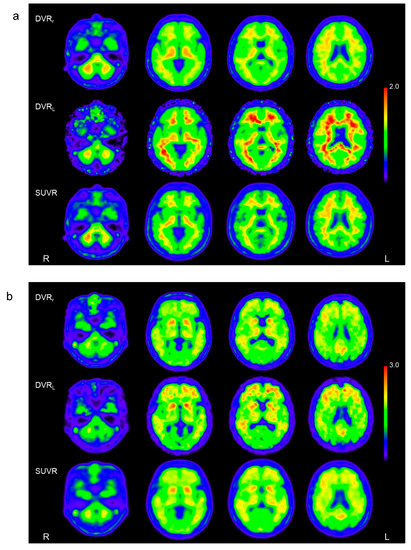

| DVRr | DVRL | SUVR | |||||

|---|---|---|---|---|---|---|---|

| CTL | eAD | CTL | eAD | CTL | eAD | ||

| Frontal | L | 1.10 ± 0.11 | 1.78 ± 0.23 †, * | 1.22 ± 0.14 | 2.14 ± 0.32 †, * | 1.20 ± 0.13 | 2.00 ± 0.30 †, * |

| R | 1.13 ± 0.10 | 1.79 ± 0.25 †, * | 1.24 ± 0.13 | 2.17 ± 0.38 † | 1.23 ± 0.13 | 2.04 ± 0.32 †, * | |

| Temporal | L | 1.07 ± 0.05 | 1.52 ± 0.16 †, * | 1.13 ± 0.06 | 1.72 ± 0.22 †, * | 1.17 ± 0.08 | 1.78 ± 0.27 †, * |

| R | 1.07 ± 0.05 | 1.53 ± 0.16 †, * | 1.13 ± 0.06 | 1.74 ± 0.23 †, * | 1.16 ± 0.08 | 1.79 ± 0.28 †, * | |

| Parietal | L | 1.11 ± 0.11 | 1.87 ± 0.22†,* | 1.18 ± 0.12 | 2.11 ± 0.31†,* | 1.18 ± 0.12 | 2.06 ± 0.32†,* |

| R | 1.13 ± 0.11 | 1.91 ± 0.27 † | 1.19 ± 0.13 | 2.19 ± 0.38 † | 1.21 ± 0.14 | 2.10 ± 0.32 †, * | |

| Occipital | L | 1.10 ± 0.05 | 1.57 ± 0.19 †, * | 1.16 ± 0.07 | 1.73 ± 0.25 †, * | 1.16 ± 0.06 | 1.73 ± 0.28 †, * |

| R | 1.11 ± 0.06 | 1.60 ± 0.17 †, * | 1.16 ± 0.08 | 1.78 ± 0.24 †, * | 1.19 ± 0.08 | 1.76 ± 0.21 †, * | |

| PCC | 1.20 ± 0.13 | 2.04 ± 0.28 † | 1.30 ± 0.16 | 2.43 ± 0.42 † | 1.31 ± 0.16 | 2.42 ± 0.41 † | |